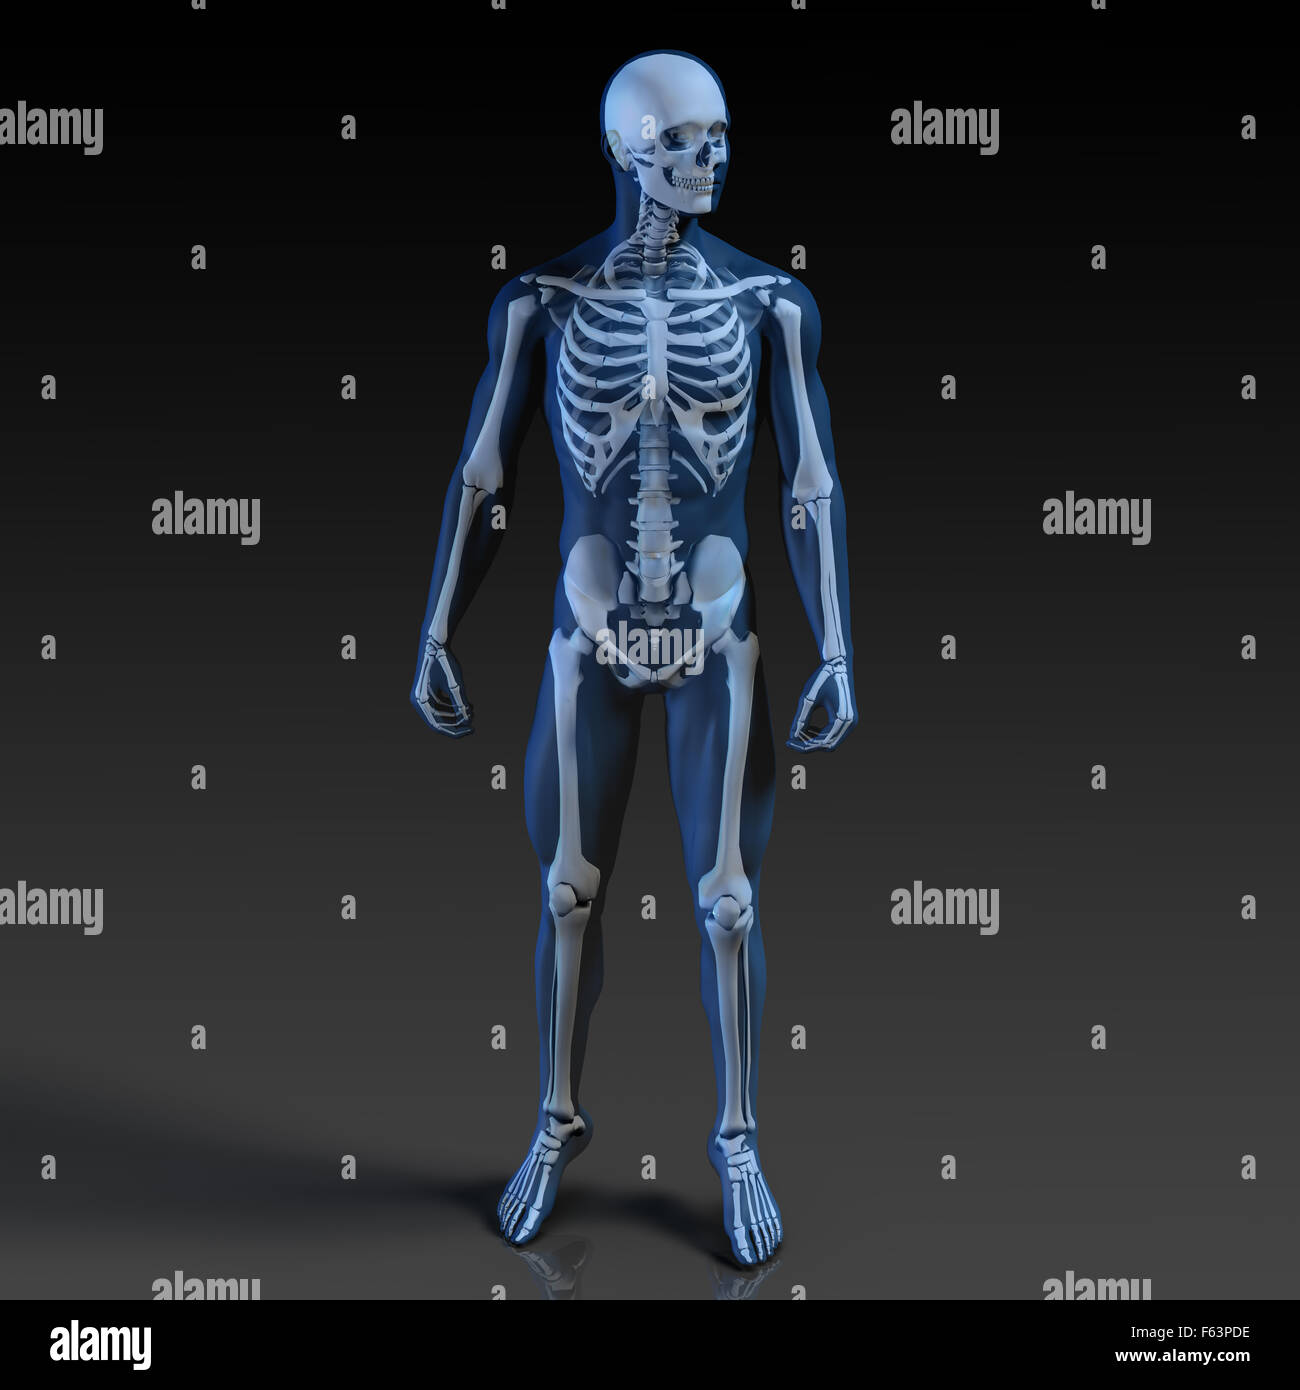

La Imagen De Rayos X Del Cuerpo Humano Fotografía De Stock - Alamy

www.alamy.es

www.alamy.es

Anatomía del cuerpo humano en vista de rayos x representación 3d. Cuerpo humano de rayos x con piel transparente representación. La imagen de rayos x del cuerpo humano fotografía de stock